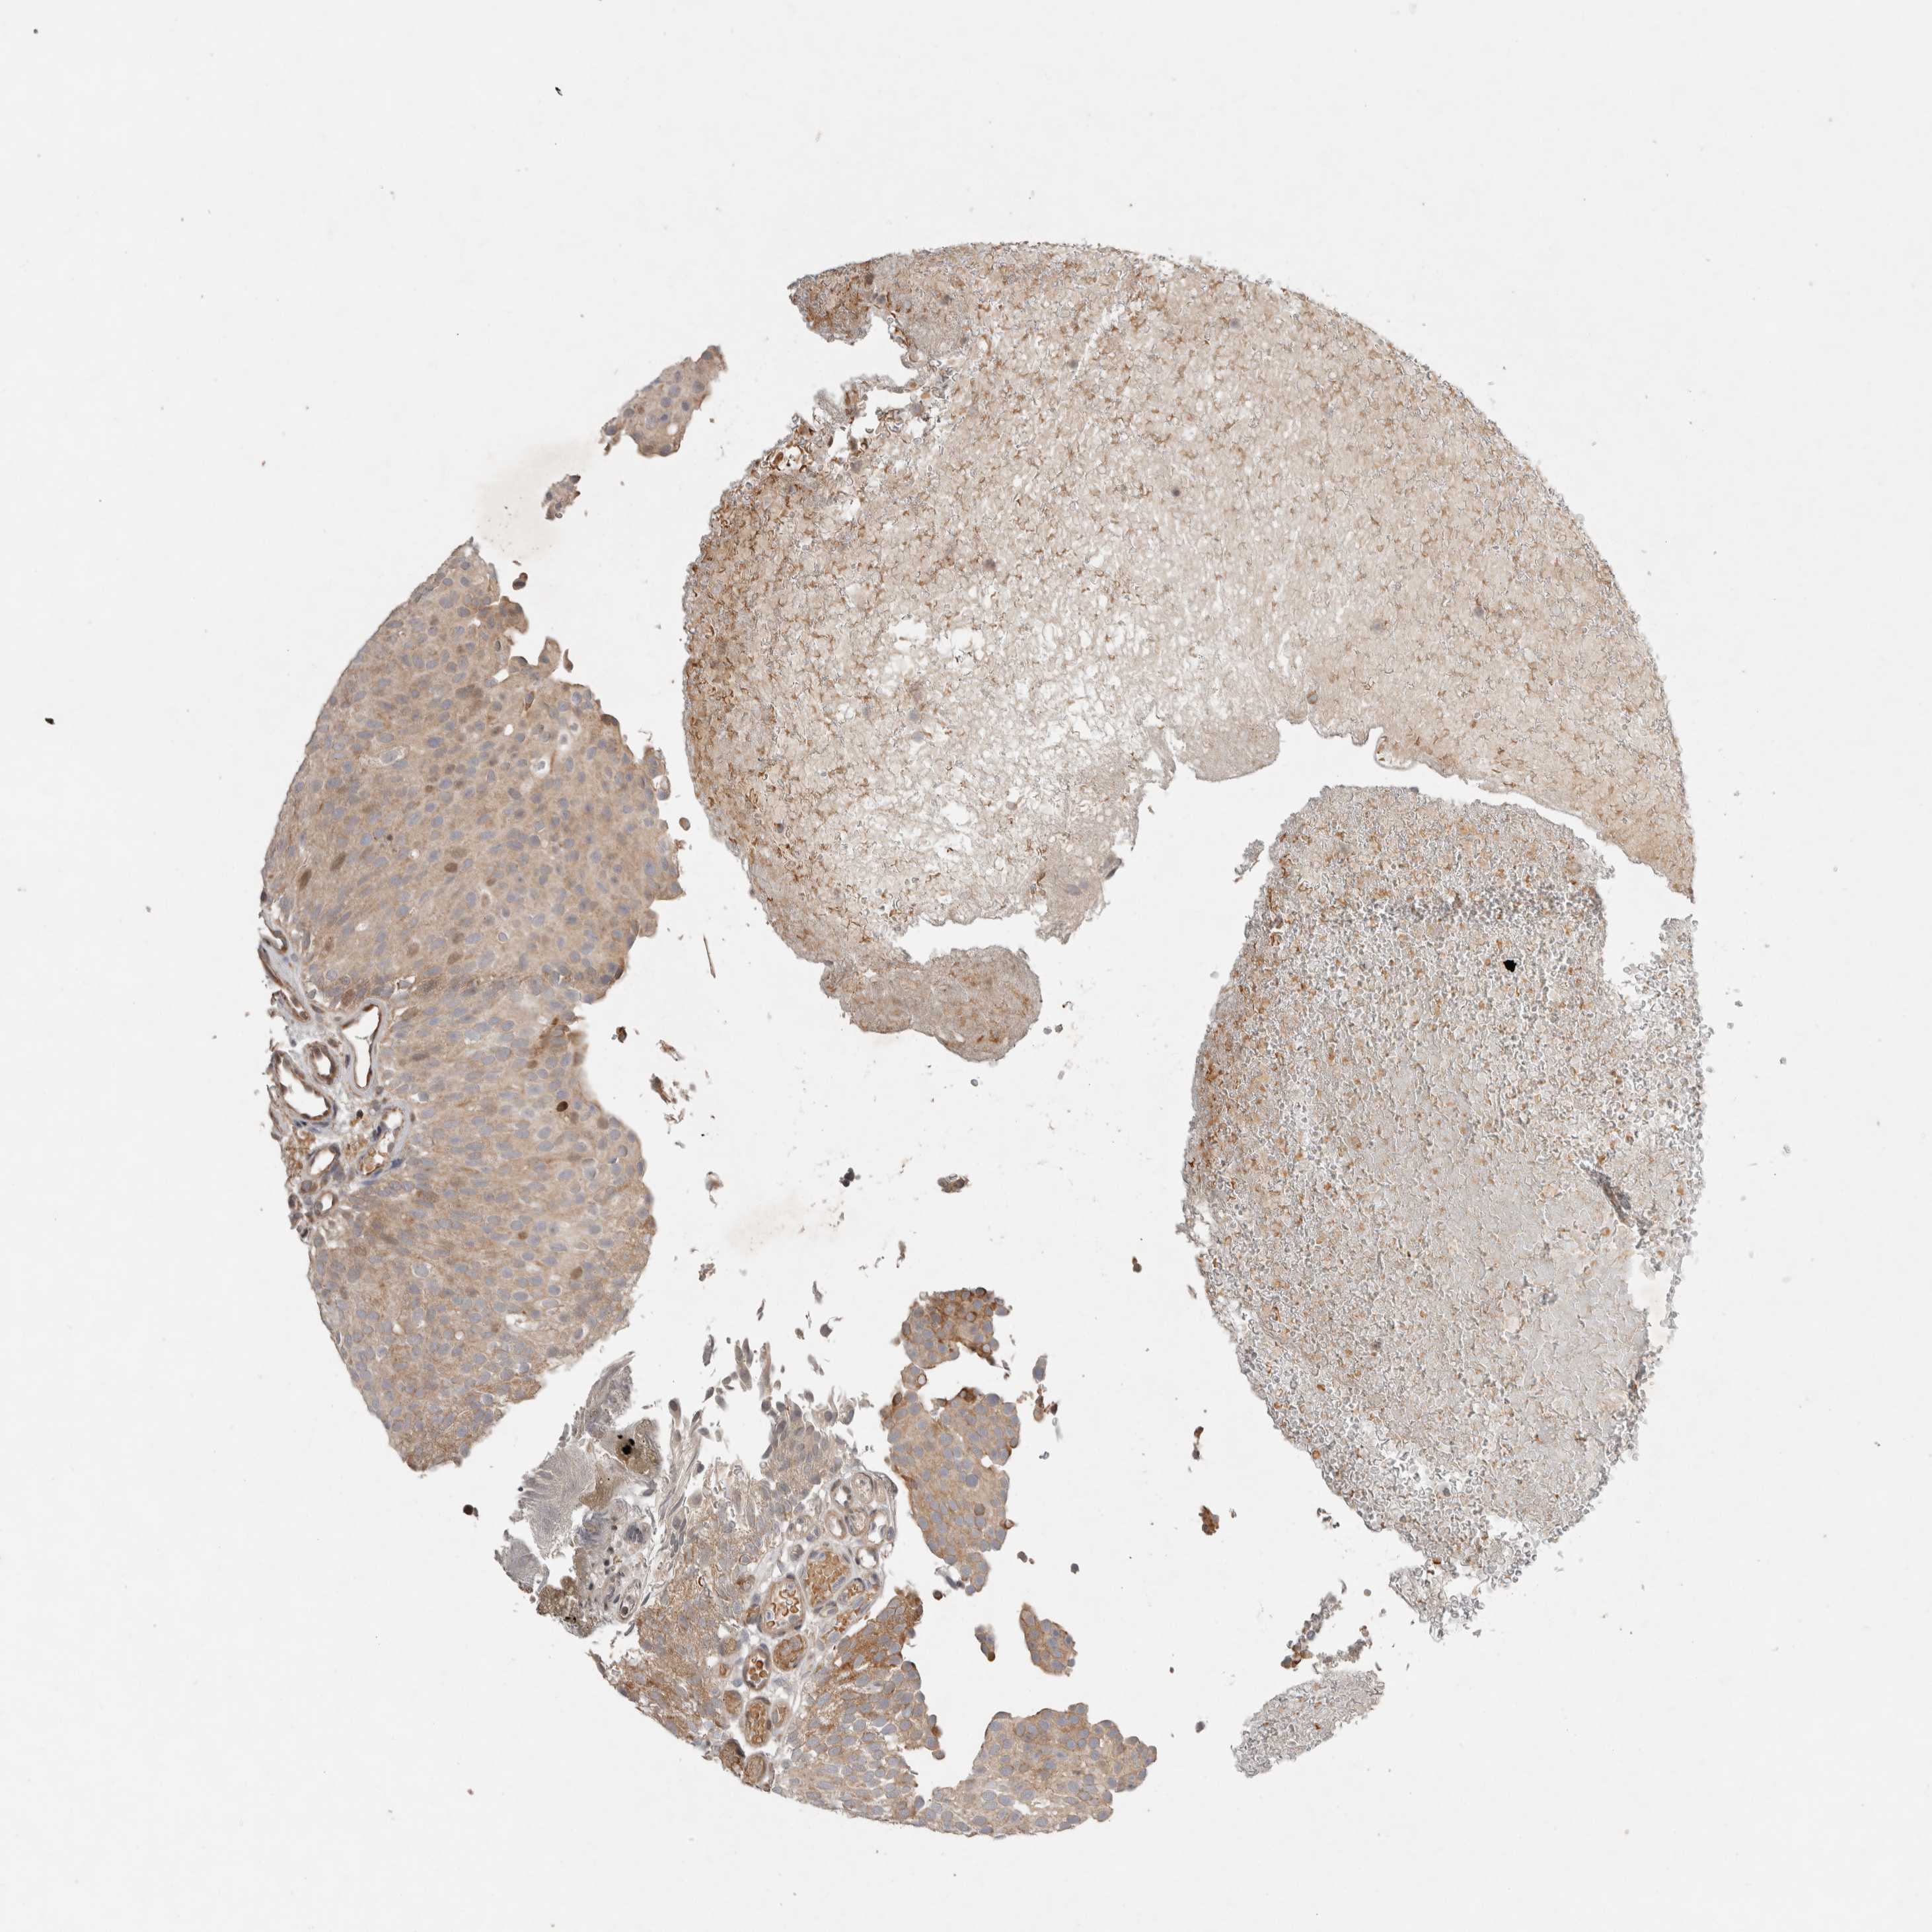

UROTHELIAL CANCER - Protein expressioni

A mouse-over function shows sample information and annotation data. Click on an image to view it in a full screen mode. Samples can be filtered based on level of antibody staining by selecting one or several of the following categories: high, medium, low and not detected. The assay and annotation is described here.

Antibody stainingi

Antibody staining in the annotated cell types in the current human tissue is reported as not detected, low, medium, or high, based on conventional immunohistochemistry profiling in selected tissues. This score is based on the combination of the staining intensity and fraction of stained cells.

Each image is clickable and will lead to virtual microscopy that enables deeper exploration of all samples and also displays staining intensity scores, fraction scores and subcellular localization as well as patient and tissue information for each sample.

Antibody HPA016496

Antibody CAB022082

Staining

High

Medium

Low

Not detected

Intensity

Strong

Moderate

Weak

Negative

Quantity

>75%

75%-25%

<25%

None

Location

Nuclear

Cytoplasmic/membranous

Cytoplasmic/membranous,nuclear

Urothelial carcinoma, Low grade

Urothelial carcinoma, High grade